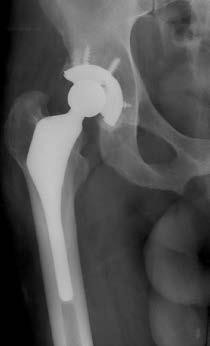

Figures 2a and 2b are the radiographs of a 56-year-old woman who has groin pain and decreased function 15 months after a total hip replacement using the posterolateral approach. Findings from the workup for infection are negative and physical examination localizes pain to the hip joint. Records show the patient underwent total hip surgery with a metal-on-metal bearing.

The differential diagnosis of pain after a total hip arthroplasty encompasses a number of etiologies, but the question is directed to a basic and essential part of the workup (ie, definitively considering and ruling in or out the possibility of deep sepsis). Radiographs may point to other, obvious sources of pain, but the orthopaedic surgeon must not overlook the possibility that deep sepsis is the predominant cause of the symptoms. Accordingly, ESR and CRP are logical next steps in the workup in this clinical scenario. Radiographs show increased anteversion of the metal socket, and pain etiologies can include psoas irritation, hip instability, or adverse tissue reaction to metal debris generated by suboptimal implant position leading to higher bearing contact stresses and/or impingement. Once other common etiologies of hip pain have been excluded such as deep infection or lumbar pathology, the most likely cause of hip symptoms should be considered. Here the evidence points to a malpositioned acetabular component. Systemic ion dissemination may occur in this patient but will not produce hip pain. Head-neck taper corrosion can generate metallic debris, but a more likely source of local metallic debris is edge loading or impingement of the metal-metal bearing. Leg length inequality can be distressing to a patient but will usually not result in hip pain. Component malposition is the best answer. Among the spectrum of clinical presentations following failed metalmetal total hip replacements, abductor damage from localized inflammation is one finding that can lead to hip instability. A reasonable treatment option is to repair the abductors as best as possible, with augmentation of soft-tissue repair using graft tissue, a large-diameter femoral head, and a constrained polyethylene liner. This is a challenging clinical scenario because chronic hip instability with deficient abductors is difficult to control and is an indication for the use of constrained components. Revision to a larger head and increased leg lengths will not address the underlying cause of instability. Hip resection is not necessary because this is not a septic total hip.